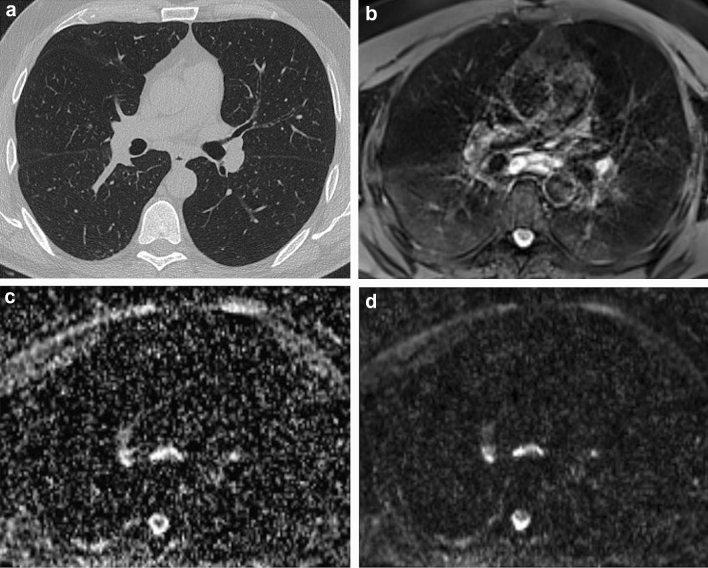

Fig. 1.

Ground-glass opacities with positive DWI. 58-year-old male. a End-inspiratory axial CT, b Free-breathing PD-weighted axial image, c Apparent Diffusion Coefficient Map, and d) DWI free breathing (b = 1000 s/mm2). Note an area of GGO on the left lower lobe that shows restricted diffusion on DWI and hyperintensity on ADC map, corresponding to an area of acute inflammation